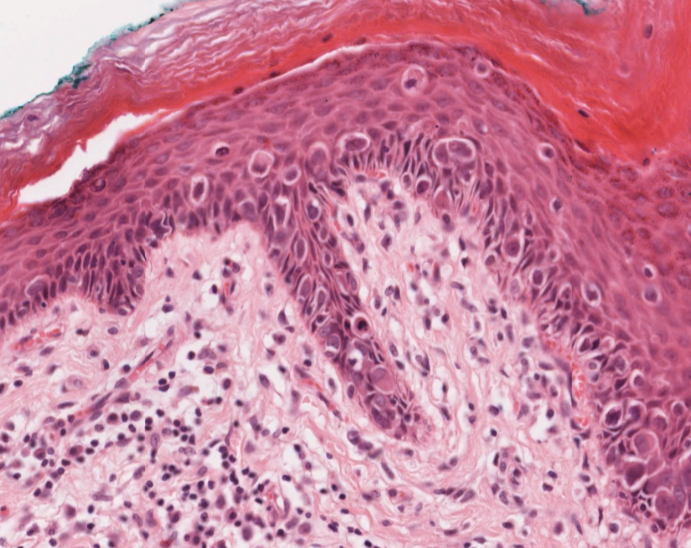

#caseoftheweek 🔬🔬🔬 What is causing this vulval lesion in this 57 year old woman? View the full slides on the Leeds Virtual pathology website here: virtualpathology.leeds.ac.uk/slides/library… #pathX #PathTwitter #gynaepath